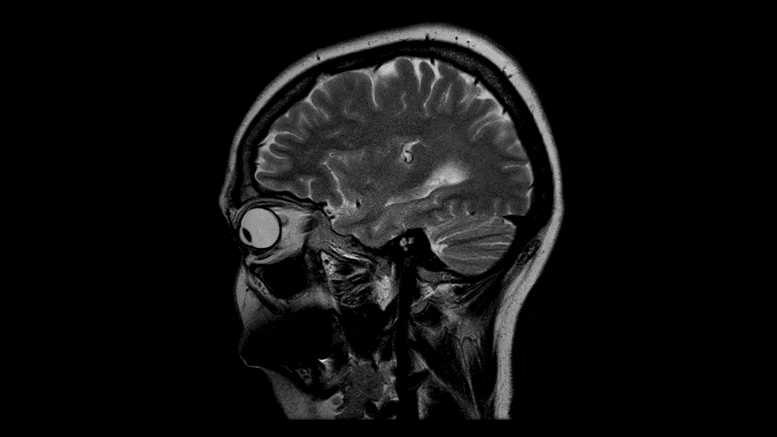

82%的COVID-19住院患者会出现神经系统问题

根据COVID-19神经功能障碍全球联盟研究(GCS-NeuroCOVID)的一项中期分析,有临床诊断的COVID-19相关神经症状的患者在医院死亡的可能性是没有神经系统并发症的患者的6倍。今天(2021年5月11日)发表在《美国医学会杂志》网络版上的一篇论文介绍了收集有关COVID-19疾病的神经系统表现的发生率、严重程度和结果的全球努力的早期结果。

GCS-NeuroCOVID是迄今为止最大的COVID-19神经系统表现的队列研究,横跨除南极洲以外的各大洲的133个成人患者点。在一组3744名住院的COVID-19成年患者中,82%有自我报告或临床捕获的神经系统症状。近10个病人中有4个报告有头痛,大约10个病人中有3个说他们失去了嗅觉或味觉。在临床诊断的综合症中--不管病人是否意识到问题,床边的临床医生可以观察到的异常--急性脑病最为常见,影响了近一半的病人,其次是昏迷(17%)和中风(6%)。

尽管早期人们担心冠状病毒能够直接攻击大脑并导致脑部肿胀和炎症--脑膜炎和脑炎--但这些事件非常罕见,在住院的COVID-19患者中发生率不到1%。研究人员分析了三种不同类型患者队列的数据--"所有COVID-19"队列,包括所有3055名COVID-19住院患者,无论他们的神经系统状况如何;"神经系统"队列,包括由GCS-NeuroCOVID联盟汇编的475名有临床确认的神经系统症状的COVID-19住院患者。以及 "ENERGY"队列,即214名住院的COVID-19患者,他们需要由神经病学顾问进行评估,并同意参加欧洲神经病学学会神经-COVID注册中心(ENERGY),该中心是GCS-NeuroCOVID联盟的正式合作伙伴。

该研究发现,预先存在任何一种神经系统疾病--从大脑、脊髓和神经疾病到慢性偏头痛、痴呆症或阿尔茨海默病等等是发生COVID-19相关神经系统并发症的最强预测因素,它们的风险增加了两倍。此外,有任何与COVID-19有关的神经系统症状,从像失去嗅觉这样看似无害的东西到像中风这样的重大事件都与六倍的死亡风险有关。即使一个病人战胜了困难并康复了,他们的长期健康前景仍然是不确定的。